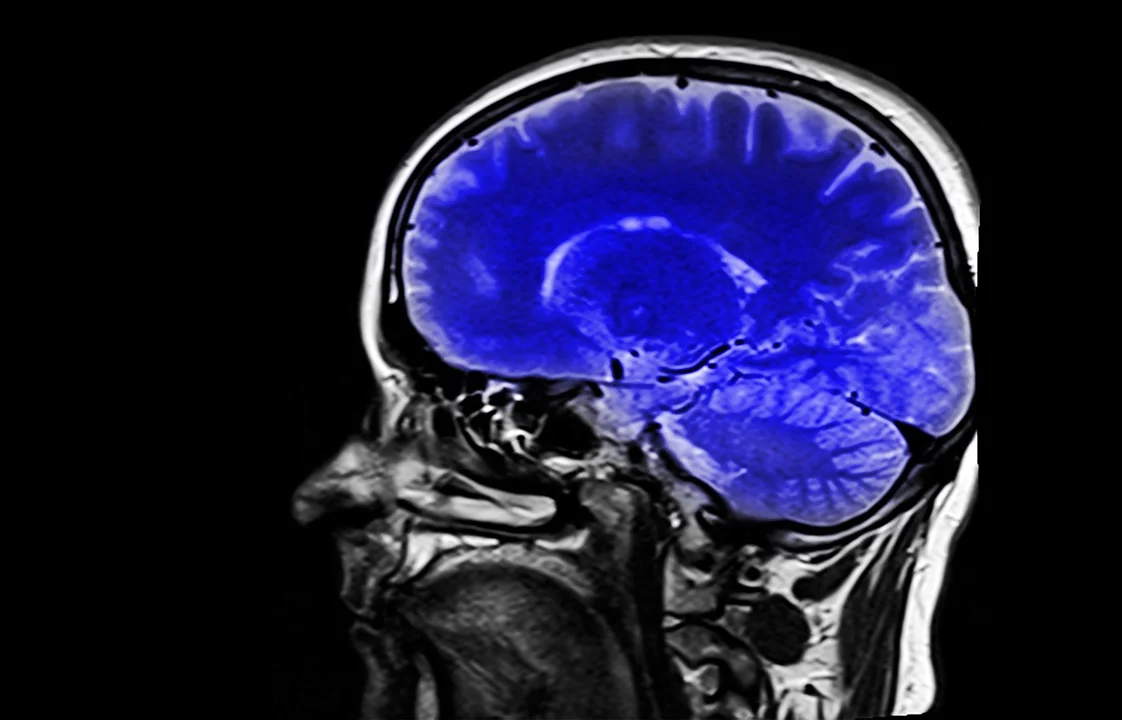

The definition of TBI is a non-degenerative, non-congenital insult to the brain from an external mechanical force, possibly leading to permanent or temporary impairment of cognitive, physical, and psychosocial functions, with an associated diminished or altered state of consciousness. If the incident causes loss of and /or confusion and disorientation longer than 30 minutes TBI is likely. It is unknown how TBI interferes with the brain and is often confused with Post Traumatic Stress Disorder PTSD because the signs often overlap. TBI can be difficult to diagnose, recognize or treat. Severe TBI can leave a person unable to function normally.

Mild Traumatic Brain Injury (mTBI) is known as a concussion. mTBI can be considered if the loss of consciousness, confusion, or disorientation from the event is less than 30 minutes. We have been hearing about mTBI in the media because of the National Football League (NFL) but not veterans who face mTBI from concussions. Assessments such as a MRI’s or CAT scans can look normal and mTBI still exist. Residual symptoms for mTBI can be seen for 18-24 months after the incident. Each mTBI event increases the chances of permanent brain damage.